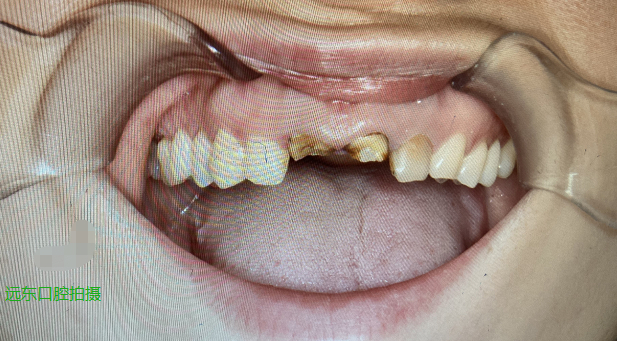

这次王女士来到了远东口腔科寻求医生的帮助,经过医生检查,王女士的两颗门牙只剩下残根,无法保留,考虑到王女士三十岁不到还很年轻,从长远角度看医生建议她这次进行种植牙。综合自身的情况和医生的讲解,王女士最后接受了医生治疗建议。

王女士缺失的是两颗大门牙,这个区域的牙齿骨壁薄,改建后牙槽骨吸收较快,吸收完成后剩余牙槽骨量往往会出现不足的情况,为种植增加了难度,修复后的美学效果也会大打折扣。

王女士的各项条件都比较好,所以进行的就是即刻种植,即拔完残根立即植入种植体,现在她只需要经过3-6个月达到骨结合后,再进行牙冠修复,大大缩短的治疗时间。虽然植入了种植体,在等待骨结合的这段时间王女士就得忍受没有门牙齿的不便和苦恼。

为了解决她的苦恼远东口腔科赵川医生为她进行了“即刻修复”,即制作一个临时牙冠修复门牙缺失,等过了骨结合期,届时取掉临时牙冠,装上种植牙的牙冠。这个临时牙冠虽然不能和真牙比,至少装上后能让王女士不必面对门牙缺失的尴尬。